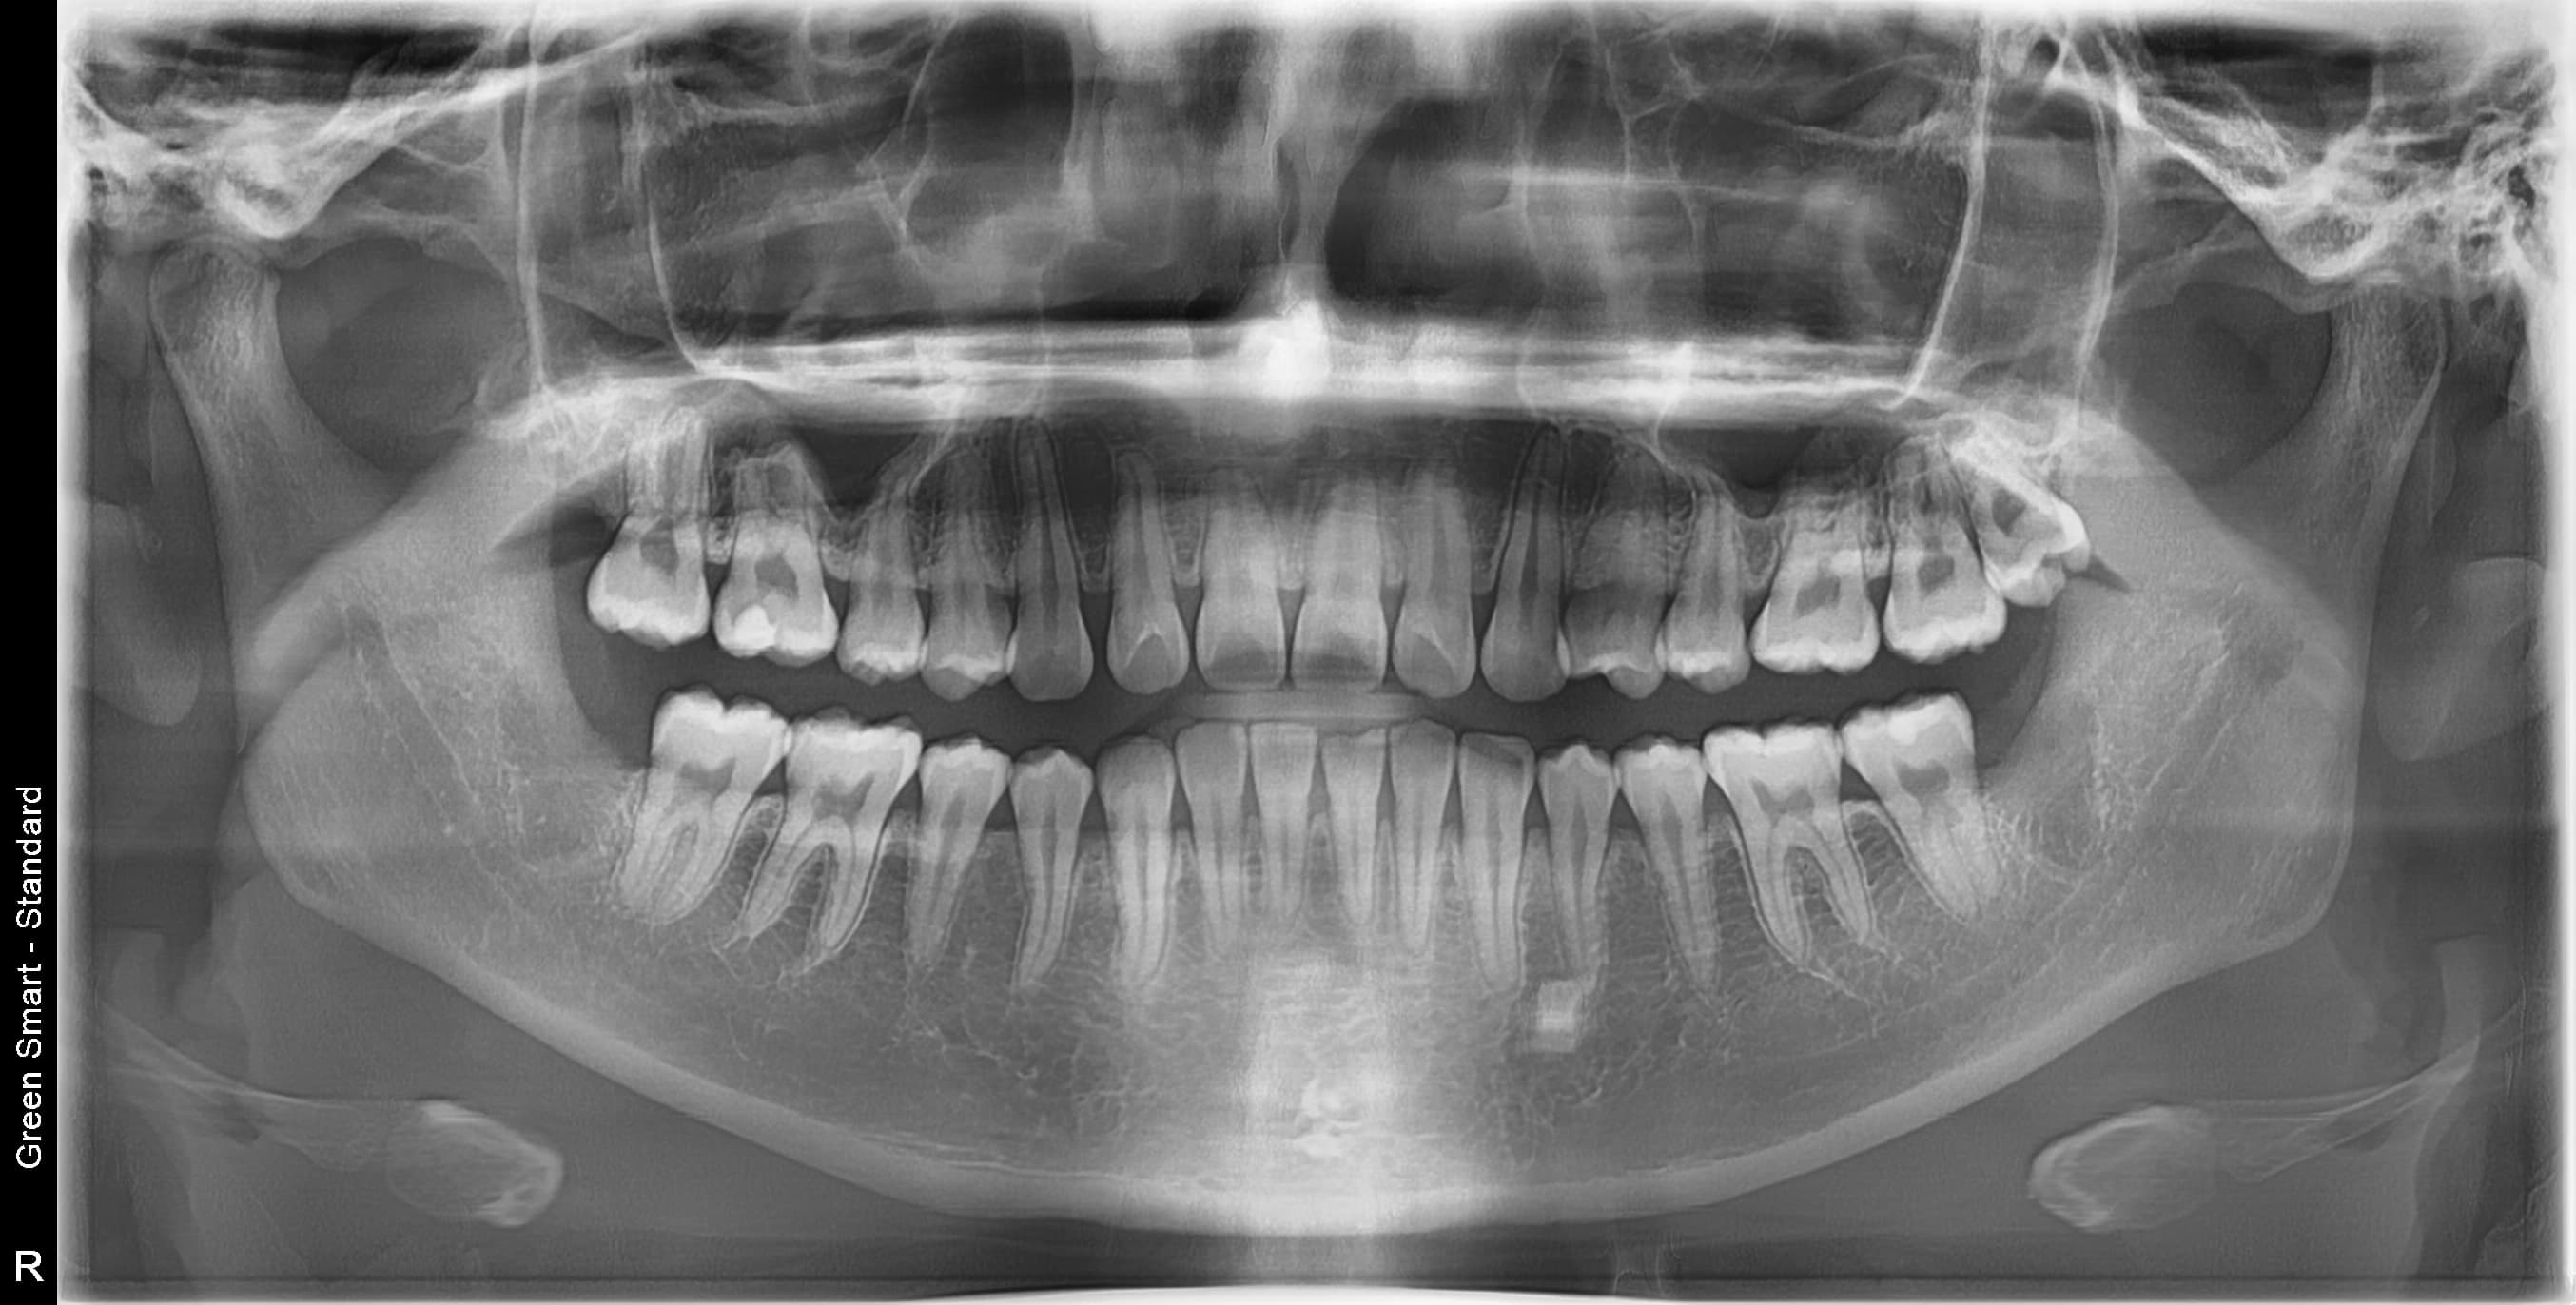

누운 사랑니

옆으로 누워 자라며 옆 치아를 압박할 수 있습니다

저위험

정상 사랑니

정상적으로 자란 사랑니도 관리가 어려워 충치 위험이 높습니다

중위험

부분매복 사랑니

음식물이 끼기 쉽고 염증이 자주 발생합니다

고위험

완전매복 사랑니

낭종 형성 가능성이 있어 조기 발치가 필요합니다

치근만곡 사랑니

뿌리가 구부러져 있어 발치 난이도가 높습니다

즉시 처치 필요

수평매복 사랑니

앞 치아를 밀어 치열 불균형과 충치를 유발합니다